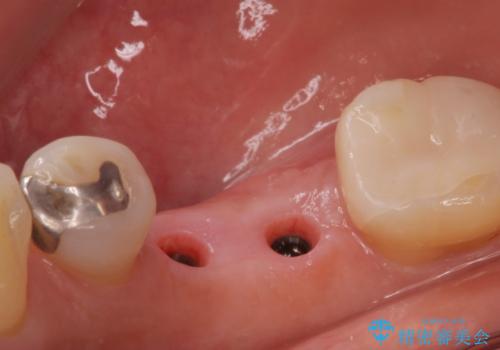

保存できない状態でしたので抜歯をして歯槽堤保存術を行いました。その後大臼歯部にインプラント治療を行いました。

欠損部に1本だけインプラントを埋入しても大きな被せ物になってしまい清掃性が悪くなるので清掃性が良くなるように2本小臼歯用のインプラントを埋入しました。